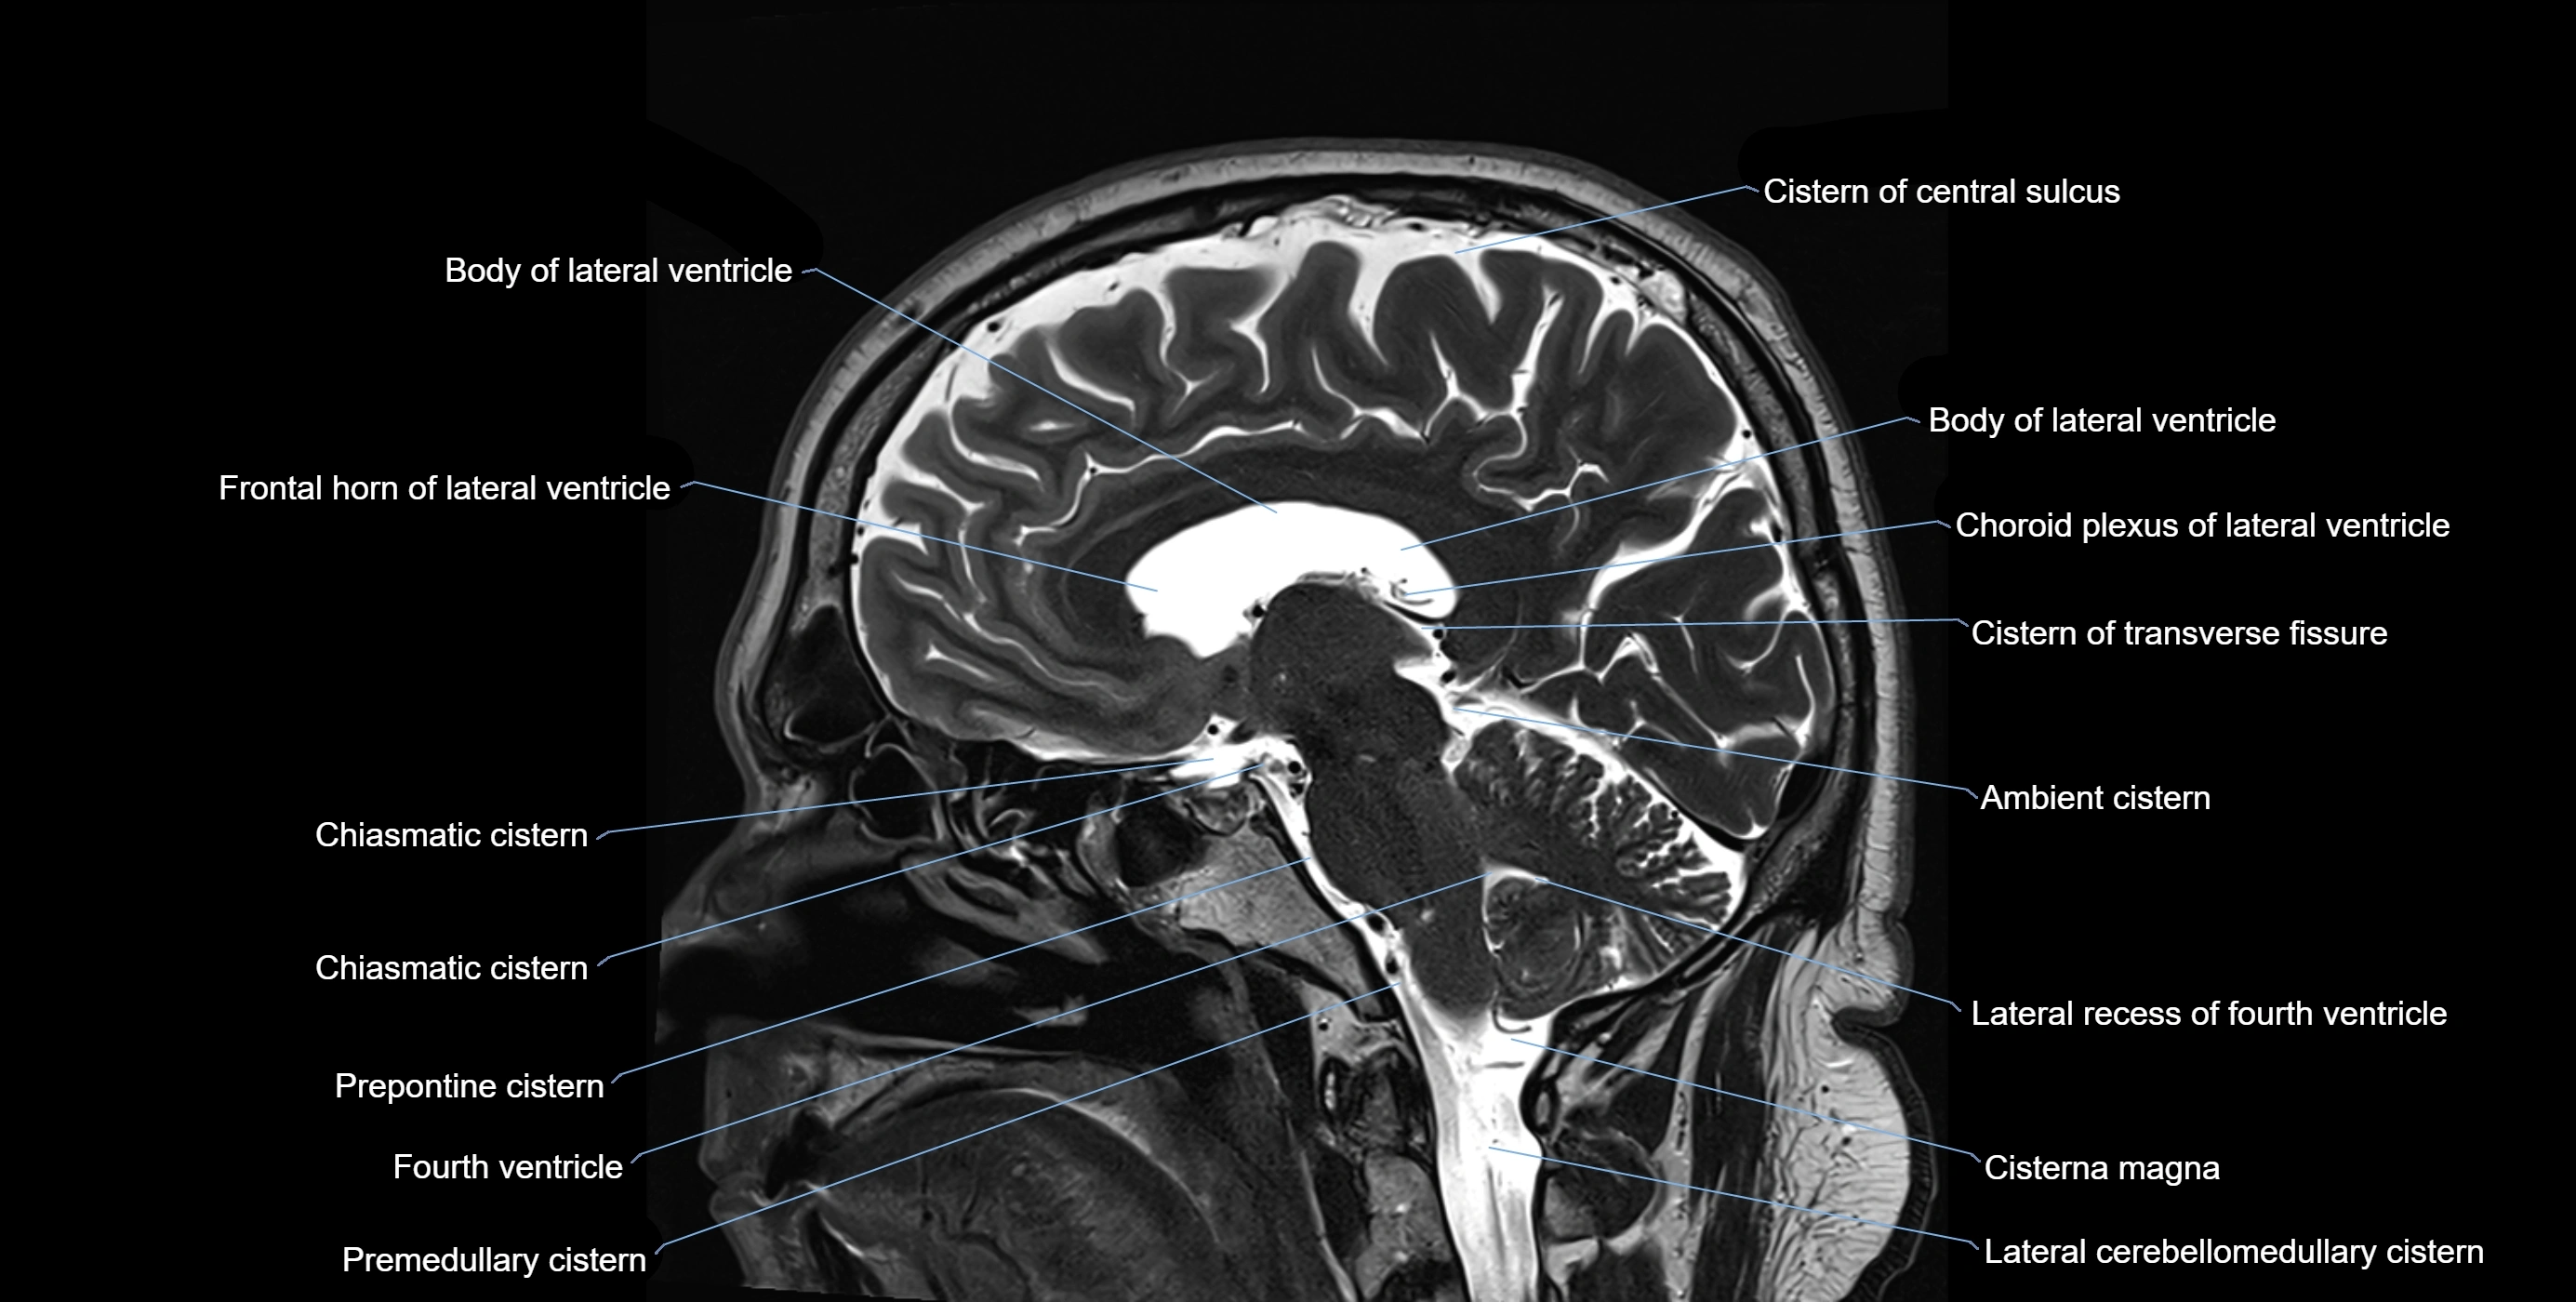

MRI images

image